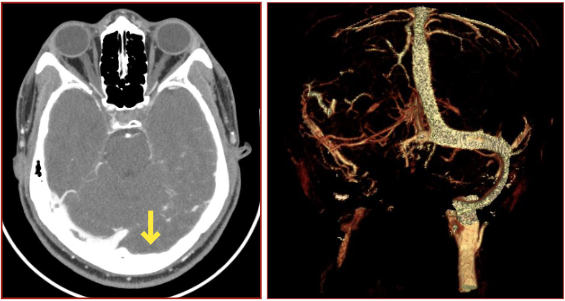

The intracranial or cerebral venous system is a network of nerves made up of two systems working together the superficial system and the deep system(1) The superficial cerebral system has sagittal sinuses and cortical veins The sinuses and the veins both drain deoxygenated blood from the surfaces of the brain's hemispheres(2)Dural venous sinus thrombosis is diagnosed on CT venography and MRV but CT plain brain is the initial radiological investigation Most of the time CT shows signs such as hyper density, hyperdense delta sign On this scan a subtle linear hyperdensity was seen in the region of right transverse sinus and confluence of sinusesApr 12, 13 · Variations in intracranial dural venous sinus anatomy have been widely reported in humans, but there have been no studies reporting this in dogs The purpose of this retrospective study was to describe variations in magnetic resonance (MR) venographic anatomy of the dorsal dural venous sinus system in a sample population of dogs with

Venous sinus anatomy appeared unusual, and thus magnetic resonance venography was performed, which identified the OS as the main drainage pathway for the entire brain, providing the sole drainage between the superior sagittal sinus and the jugular veins through the marginal sinus Both the transverse and sigmoid sinuses were hypoplastic, andThe dural venous sinuses (also called dural sinuses, cerebral sinuses, or cranial sinuses) are venous channels found between the endosteal and meningeal layers of dura mater in the brainBACKGROUND AND PURPOSE Patients with intracranial hypotension (IH) demonstrate intracranial venous enlargement with a characteristic change in contour of the transverse sinus seen on routine T1weighted sagittal imaging In IH, the inferior margin of the midportion of the dominant transverse sinus acquires a distended convex appearance;